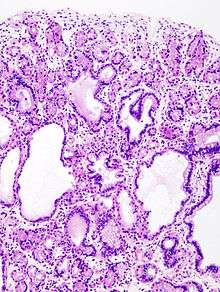

The polyps on endoscopy are usually tiny, numerous and sessile,[3] and usually scattered throughout the fundus of the stomach, where parietal cells are more numerous. They have the same colour as the gastric mucosa, and never have a stalk.[4] When the polyps are biopsied, the pathology typically shows shortened gastric pits, and both superficial and deep cystic lesions in the fundic glands, lined by all three types of cells of acid-producing mucosa: mucous, parietal and chief cells. As sometimes parietal cell hyperplasia may develop deep dilations of gland,[5] one should be really strict in the diagnosis of FGPs (i.e. the presence of deep and superficial dilations). Infrequently, the two lesions may coexist.[3] Foci of dysplasia can sometimes be seen.[4]